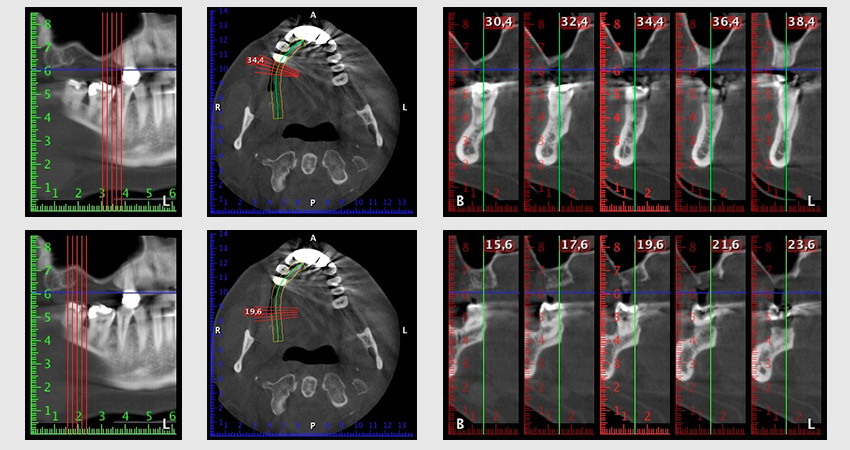

La paciente de 59 años presentaba una periodontitis avanzada, describía una desagradable sensación y un mal gusto proveniente del primer cuadrante. La evaluación clínica mostró en general marcadas profundidades de bolsa y una degeneración ósea muy avanzada en las regiones 16 y 14. El estudio radiológico corroboró estos resultados (figura 1). Las piezas dentales 16 y 14 no podían conservarse.

Imagen 1: Ortopantomografía con retirada ósea en las regiones 16 y 14*